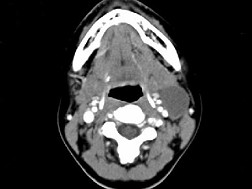

[单选题]女,57岁,颈部不适,CT如图所示,最可能的诊断是()A.咽囊囊肿B.鳃裂囊肿C.甲状舌管囊肿D.颈部淋巴管瘤E.颈部神经鞘瘤

[单选题]女,57岁,颈部不适,CT如图所示,应诊断为()A.咽囊囊肿B.鳃裂囊肿C.甲状舌管囊肿D.颈部淋巴管瘤E.颈部神经鞘瘤